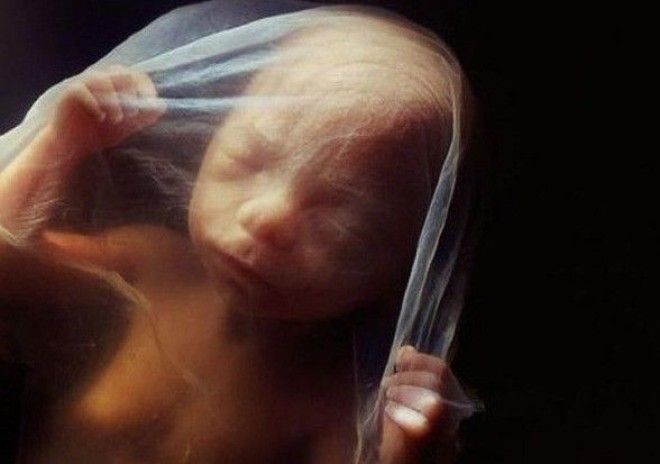

10 недель. Веки уже полуоткрыты. В течение нескольких дней они сформируются полностью.

10 недель. Малыш уже использует руки для изучения окрестностей